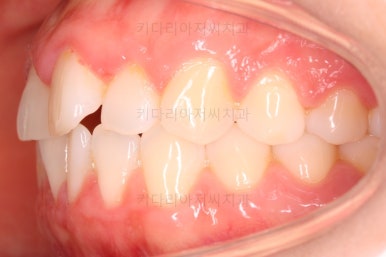

왼쪽 사진들이 부산나비앞니교정 치료 전 모습, 오른쪽 사진들이 치료 후의 모습입니다.

가지런해진 느낌이 전후 비교해보니 훨씬 느껴지실 거에요.

이상 부산나비앞니교정 키다리아저씨치과에서 시행한 나비치아를 가진 환자분의 앞니 부분교정을 치료한 사례였습니다.